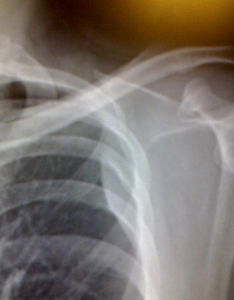

局限性的胸膜增厚和粘連,常見於肋膈角處,使肋膈角變鈍、變淺或變平。透視下可見該處橫膈運動減弱。胸膜亦可有較廣泛的層樣增厚及粘連,若厚度不大,又位於前胸壁或後胸壁,則可以不引起明顯的X線改變,當胸膜增厚達到一定厚度時,則使患側肺野密度增高,當轉至切線位時,可在胸廓內緣和肺野之間有一層邊緣清晰的銳利陰影。大量的胸膜增厚和粘連可引起肋間隙的縮小,縱隔向患側移位,脊柱向對側側凸,橫隔上升。病變廣泛者可使患例肺門上提,氣管向患側移位。另有一種索狀胸膜粘連,在氣胸和肺受壓萎陷時較易見到,顯示為胸壁與一處肺表面之間有一條邊緣清晰的索狀緻密影相連。索狀胸膜粘連往往是貼近胸膜的肺部病灶所引起的胸膜改變。常見於結核並好發於上肺。透視下觀察橫膈運動可以鑑別局限性胸膜增厚和粘連與少量胸腔積液.治療